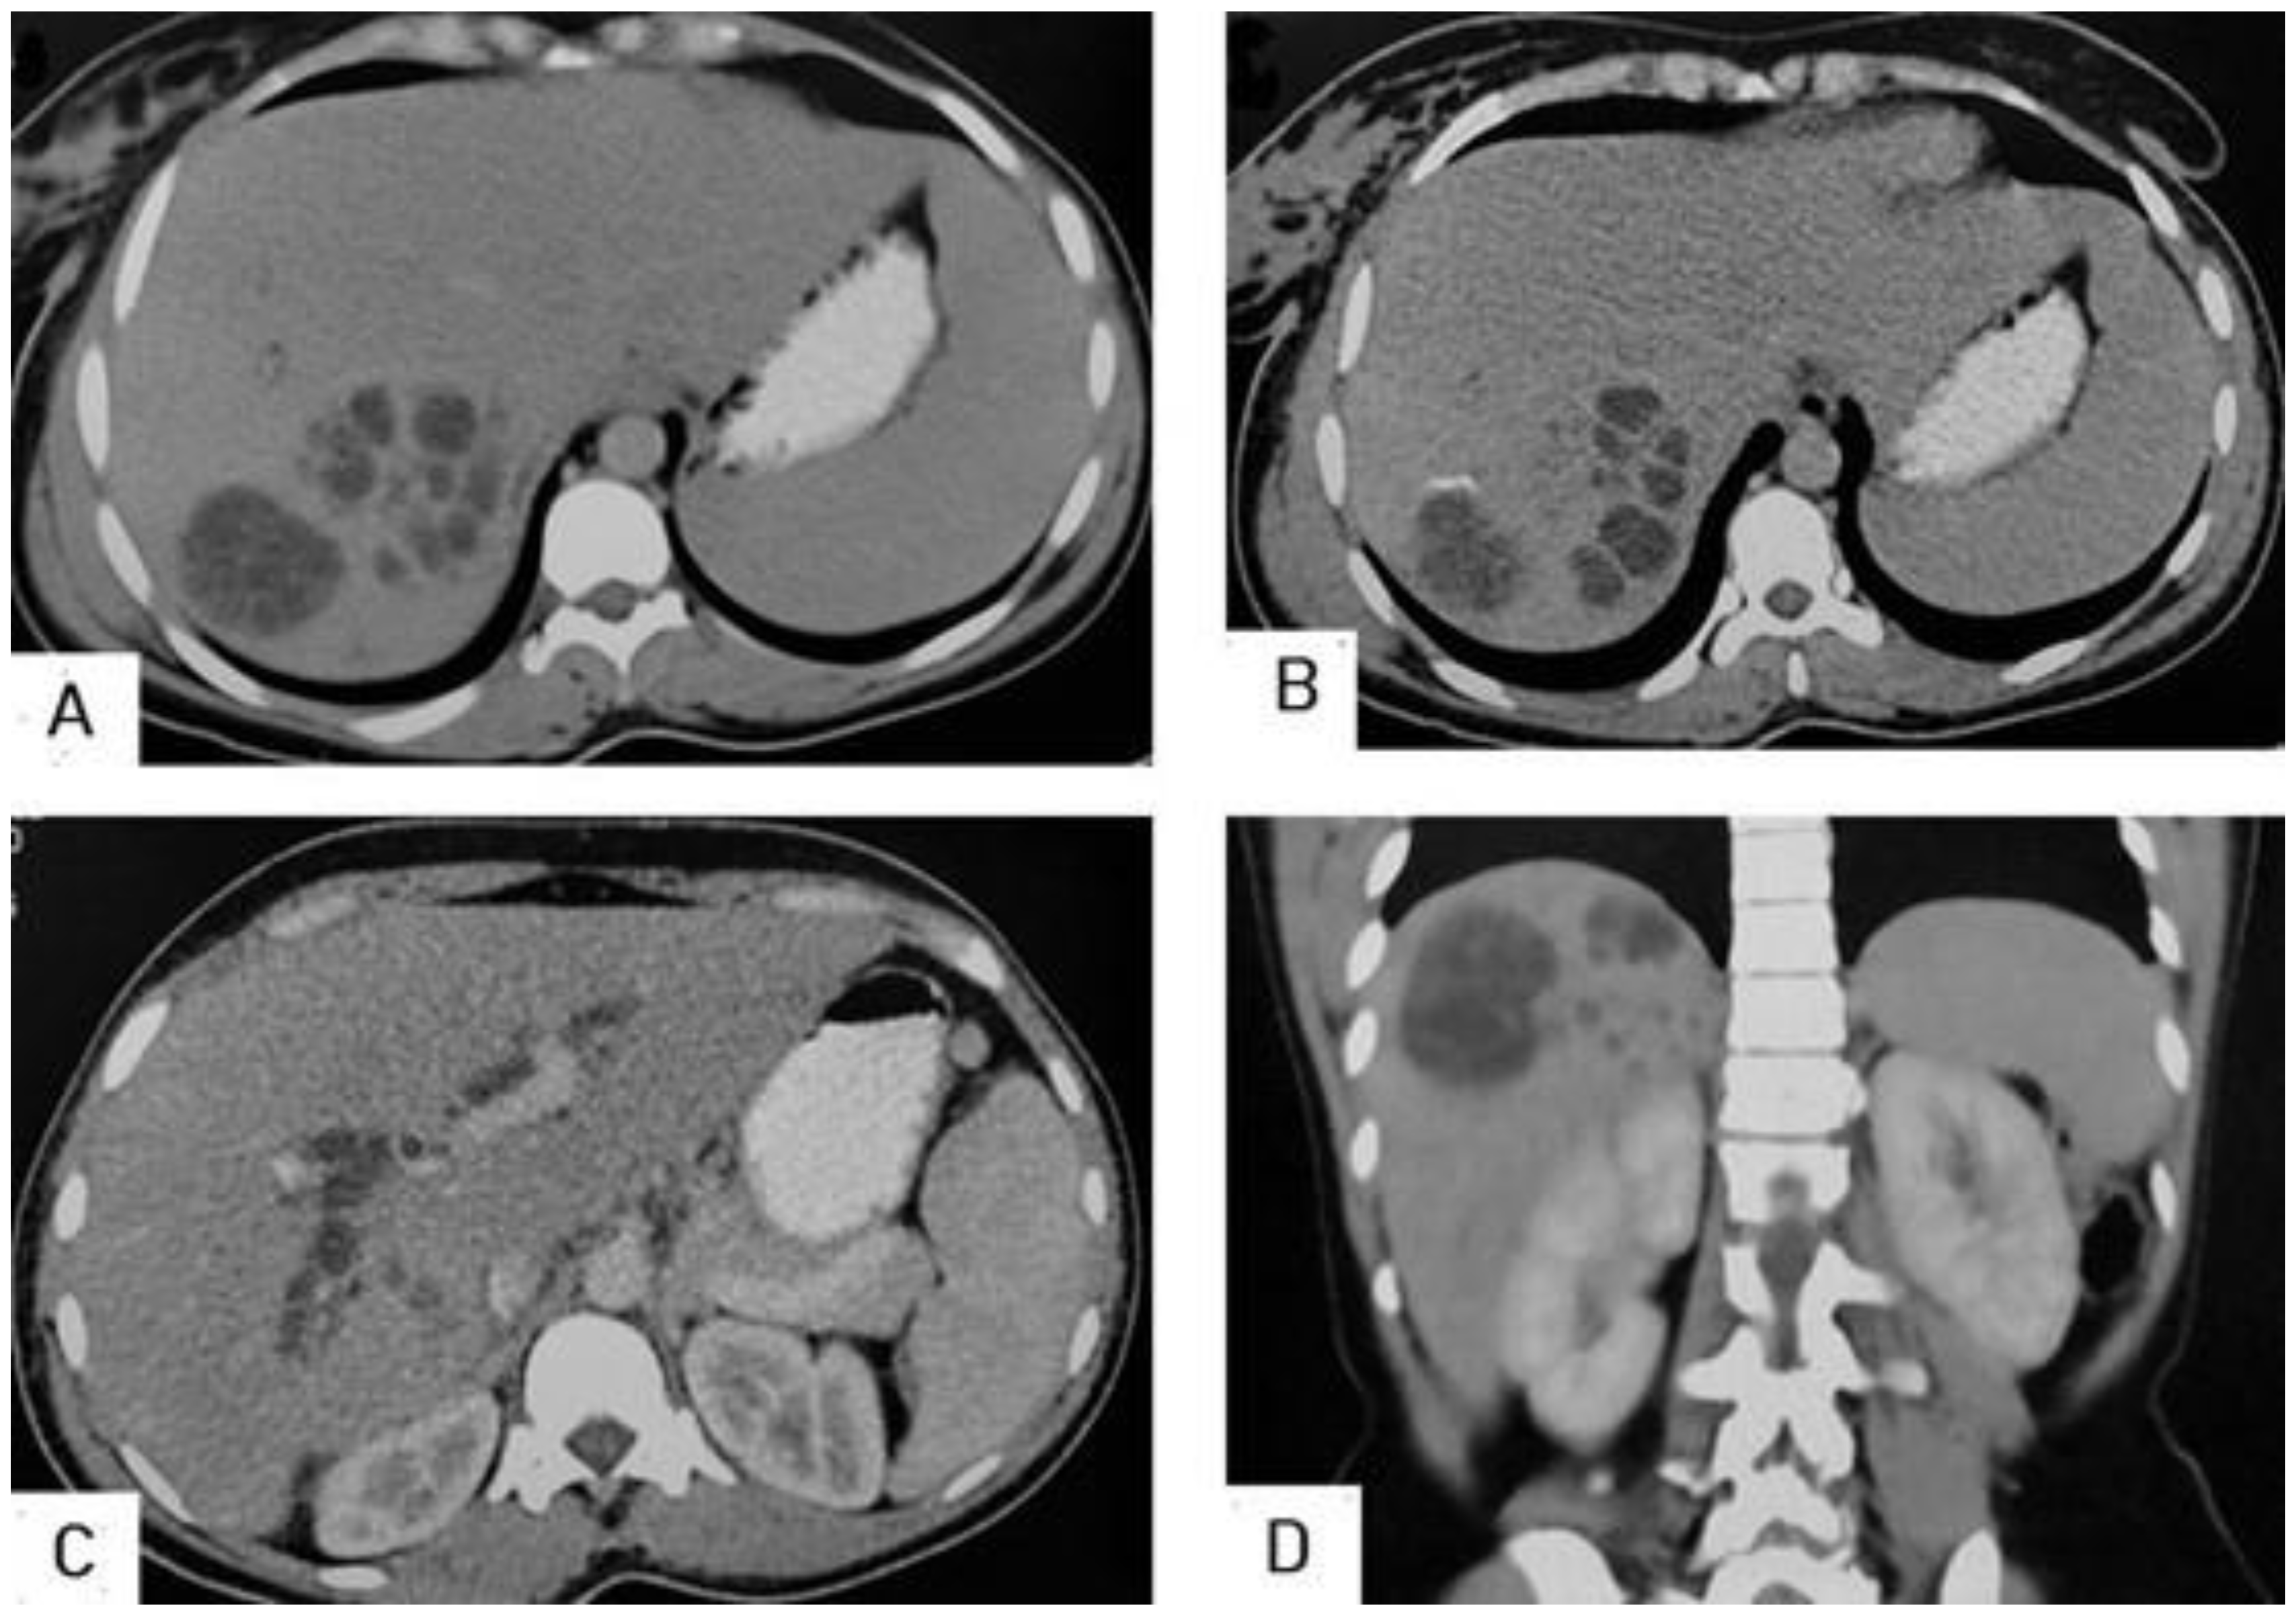

What's the Diagnosis?